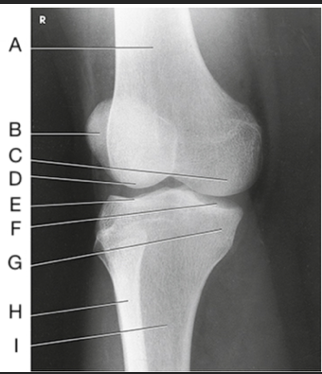

Name this projection

AP knee

Where does the CR enter for this projection?

½" inferior to patellar apex

If the patient is sthenic (19-24 cm) how is the CR directed?

0 degrees (perpendicular to IR)

Label the image: A

femur

Label the image: B

patella

Label the image: C

lateral femoral epicondyle

Label the image: D

lateral femoral condyle

Label the image: E

Lateral tibial plateau

Label the image: F

intercondylar eminence

Label the image: G

head of fibula

Label the image: H

tibia

Label the image: I

fibula